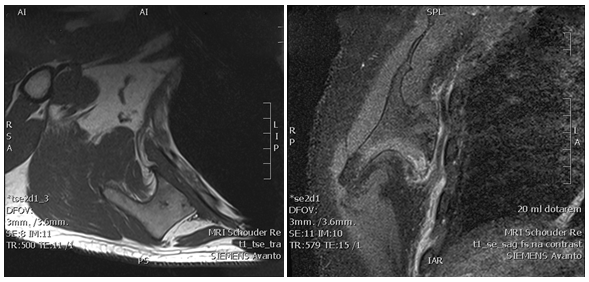

In our outpatient department a 33-year-old male presented with complaints of continuous pain around his right shoulder and scapula. The pain developed gradually over the last 2 years, making it impossible to sleep on his right shoulder and he had complaints of pain during daily labour. When moving his right shoulder, crepitation was noted by the patient around the right scapula. Family history was not contributory and there was no history of trauma. A clinical examination showed an asymmetry of his scapulae with a wing-like prominence of his right scapula (Figure 1). Scapulothoracic crepitus was noted when abducting his right shoulder. A full range of motion was found in both shoulders. Radiographic evaluation showed an irregular bony structure extruding from the scapula (Figure 2). Computed tomography (CT) revealed an osteochondroma along the medial border on the ventral surface of the right scapula (Figure 3). In addition a magnetic resonance imaging (MRI) was performed, showing a bone lesion originating from the anterior side of the scapula with slight bursa formation, most likely to be an osteochondroma (Figure 4). There were no signs of malignant transformation. Since the lesion prevented the patient from performing his job and the complaints of his shoulder worsened over time, surgical resection was proposed.

Figure 4 MRI of the right shoulder showing a osteochondroma of the scapula with a small cartilage cap.